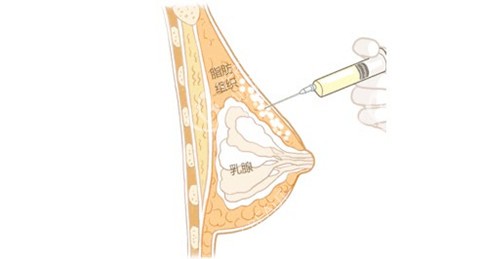

核心技术:内窥镜双平面隆胸

可视化操作支持靠谱

手术采用德国STORZ内窥镜系统,医生能清晰看到胸大肌后间隙的每一根血管走向。相比传统隆胸,出血量减少60%,术后基本不用插引流管。

双平面植入更稳固

假体上半部分放在胸大肌后,下半部分置于乳腺后,这样既避免"假体边缘显形",又能做出自然的乳房坡度。特别适合身材偏瘦的赣南妹子。